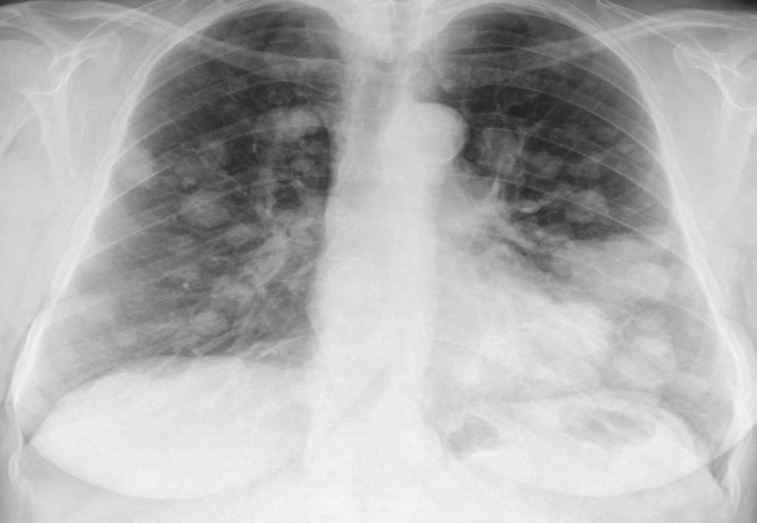

Lung mets (RCC mc cause)

variable in size, well defined, radio-opacities, diffuse, bilateral

Canonball appearance